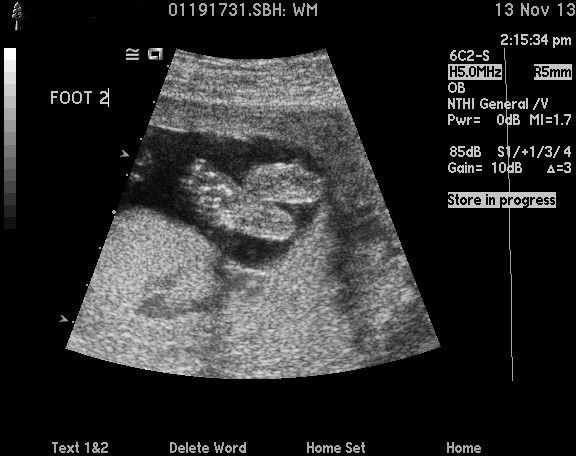

Incoming Baby! (part 2) – Wooshy

Posted by Barniferous in Uncategorized on March 6, 2014

On our second appointment, The Doctor pulled out a small microphone for listening to the baby’s heartbeat. The Wife laid down on the exam table, and The Doctor put the microphone on the still small baby bump. Instantly we started hearing the distinct “woosh woosh” sound made by a fetal heartbeat. It was one of the most powerful things I had ever experienced. Something that I did had created a tiny heartbeat inside The Wife. We were listening to our potential future child.

One of the challenging things about being pregnant is how to refer to the baby. Early on do you call it a fetus? A baby? The child? It? Our future child? To make things easier, we decided to give “it” a name. We named the future potential human “Wooshy” after the sound that the heart made. We used the nickname Wooshy right until about an hour before delivery. Our friends thought this was pretty clever, but it drove my mother crazy.

Note to first time parents – find a way to record the sound of your baby’s heartbeat when you hear it. You will want to listen to that sound again.